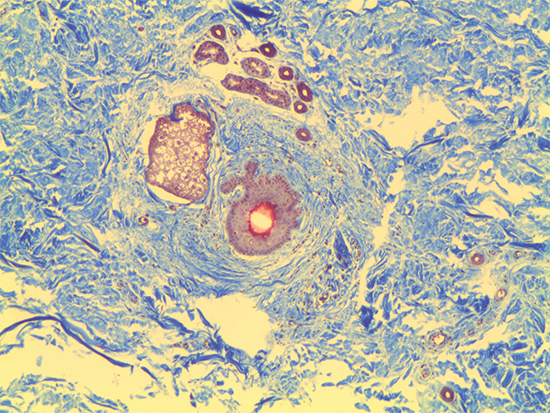

In Figures 1 – 4, the samples for inspection are 3D Skin Culture Models with a Trichrome Stain, which was cultured and prepared by Zen-Bio Incorporated located in Research Triangle Park, North Carolina, US. In Figure 1, it is clear to see cellular components surrounded by the extracellular matrix (ECM), which holds the tissue together. Within the ECM are the interstitial matrix and basement membrane, where polysaccharides and fibrous proteins reside and act as a compression buffer against external stress. Within the basement membrane reside a number of sheets that are stacked upon one another with epithelial cells resting between. To clearly see the polysaccharide gel and epithelial cells, it is best to use a high magnification infinity corrected objective. The tissue matrix is the surrounding blue stained material, the cells and cellular membrane are marked by the purple stains, and within each cell is a smaller white and partially red stained region that marks denser intracellular material, such as mitochondria and the nucleus.

Figure 1 was captured using #59-876 5X M Plan Apo Objective. This infinity corrected objective has a numerical aperture of 0.14, field of view on a ½" sensor of 1.28mm x 0.96mm, and resolving power of 2μm. Since typical human cells are roughly 10μm in size, the objective specifications for #59-876 make it the ideal choice.

Figure 1: Trichrome Stain of Dermal Tissue Samples at 5X Magnification Using #59-876 Objective